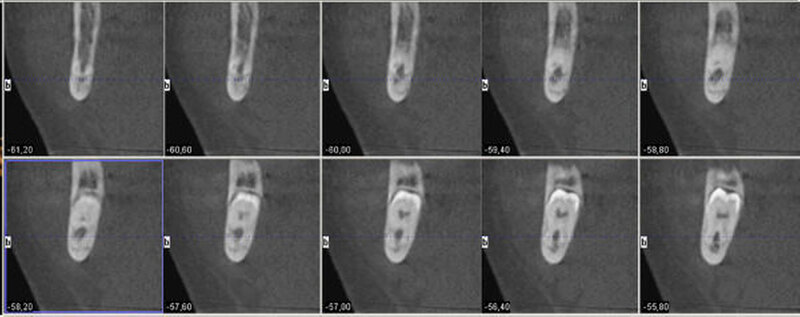

Aufgrund der engen Lagebeziehung der Weisheitszähne zum Nervus alveolaris der jeweiligen Seite wurde zur weiterführenden Diagnostik eine digitale Volumentomografie durchgeführt.

In der 3-D-Aufnahme bestätigte sich der Verdacht, dass der Nerv zwischen den Wurzeln hindurch zog, wobei beim Zahn 48 die Wurzeln den Nerv komplett umklammerten (Abbildungen 3 und 4). Nach Inzision auf dem aufsteigenden Unterkieferast mit Entlastung an den Zähnen 37 beziehungsweise 47 wurden der Knochen und im Weiteren die Weisheitszähne dargestellt. Die Kronen wurden von der Wurzel getrennt, die Wurzeln separiert und sukzessive entfernt, wobei die Integrität der Nerven auf beiden Seiten erhalten blieb (Abbildung 5).

Eine Verletzung des Nervus alveolaris inferior bei Weisheitszahnentfernung findet sich überproportional häufig in Fällen, in denen auf der Panoramaschichtaufnahme Zeichen zu erkennen sind, wie eine Veränderung des Verlaufes des Nervus alveolaris inferior (Abbildungen 1 und 2), bei überlagerungsbedingter erhöhter Transluzenz im Bereich der Überprojektion von Wurzel und Nerv und bei Unterbrechung der kortikalen Begrenzung des Nervkanals [Blaeser et al., 2003]. Alle diese Kriterien lagen im vorliegenden Fall vor. In der weiterführenden digitalen Volumentomografie ist zu erkennen, wie der Nerv zwischen den Wurzeln liegend hindurchzieht.

Man kann den Nerv-Verlauf im DVT besser beurteilen als in der Panoramaschichtaufnahme.